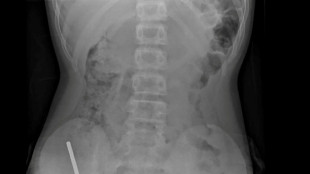

Ecuadoran President Daniel Noboa said Thursday that an unknown assailant had attempted to poison him with chocolate and a jam laced with chemicals, gifted to him at a public event.

Noboa told CNN the presence of three "highly concentrated" toxic substances in the sweets "could not have been accidental," saying his team had proof to back up his claims.

The 37-year-old president said the toxic substances could not have come from the products themselves or their packaging.